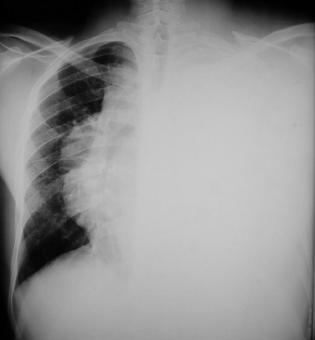

• Una Radiologia de Tórax control demostró, la presencia de derrame pleural derecho y aumento en tamaño de la masa mediastinal, el tubo de tórax (en la base pulmonar izquierda) drena un quilotorax de 3000 cc diarios,con espacio pleural libre, sin lesiones pulmonares izquierdas visibles.